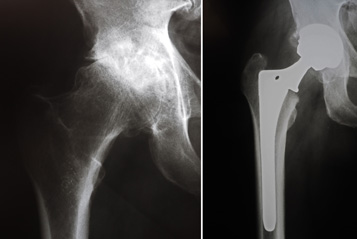

(Left) In this x-ray of a normal hip, the space between the ball and socket indicates healthy cartilage. (Right) This x-ray of an arthritic hip shows severe loss of joint space.

X-rays before and after total hip replacement. In this case, non-cemented components were used.